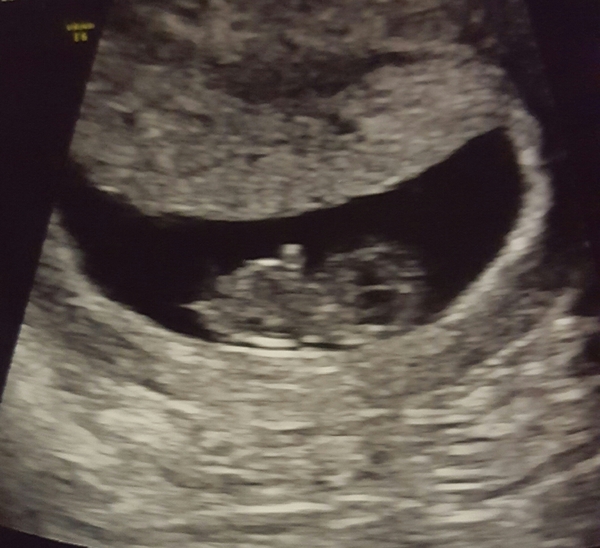

Had my early scan ladies and all is well (pic attached but just looks like a jellybean with little stumpy arms haha). They put me a few days ahead at 9+1 but I'm sticking with my dates for now (8+4).

Morning everyone, had our scan last night, after all my worries that there was nothing in there saw little 8+4 bean with 170bpm heartbeat and even got to watch the cord and heartbeat doppler. It was such a huge relief after a miscarriage this Summer. Nearly put a pic on but realised all the pics on my phone have my name and everything on there. I was one day ahead of where I thought so looks like my dates were bang on. Booking in this Friday at what will be 9 weeks.